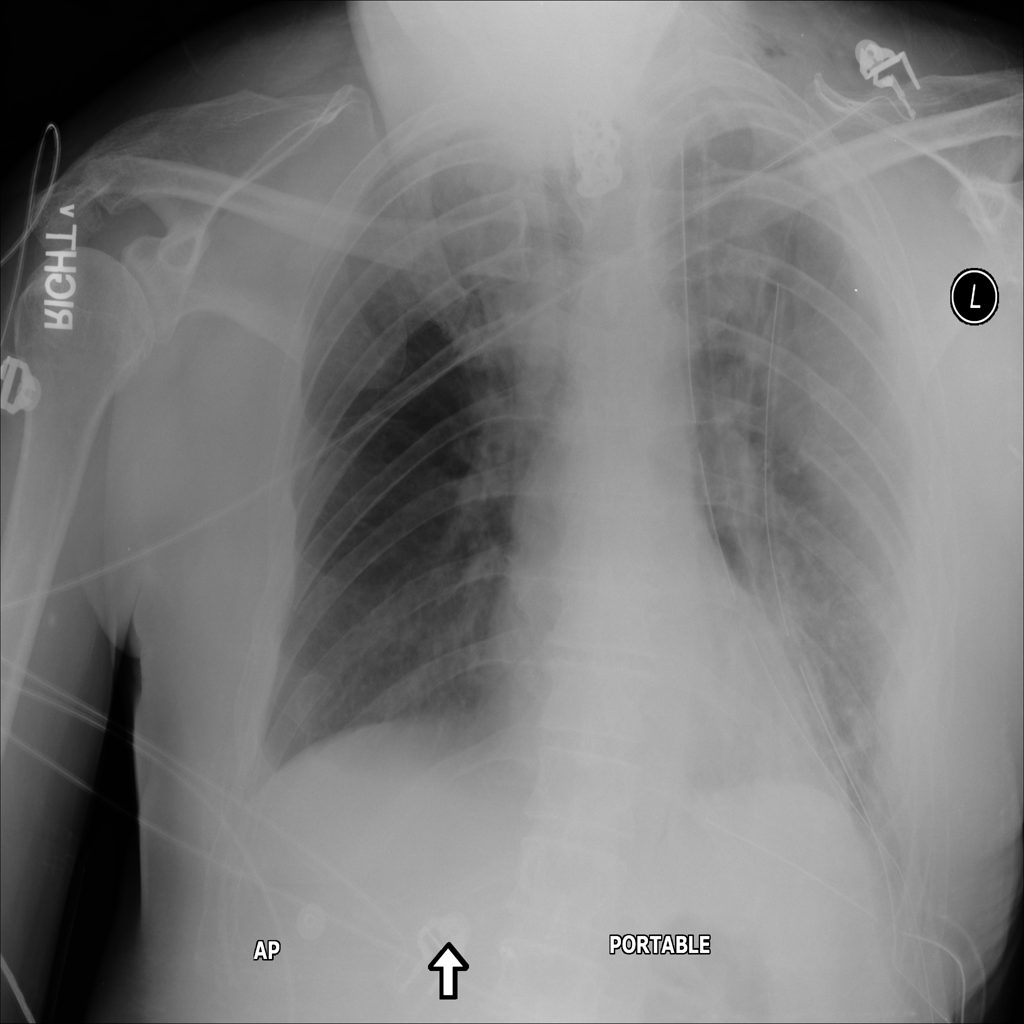

PAT-531A · IMG-006Consolidation

PAT-531A · IMG-006

PA